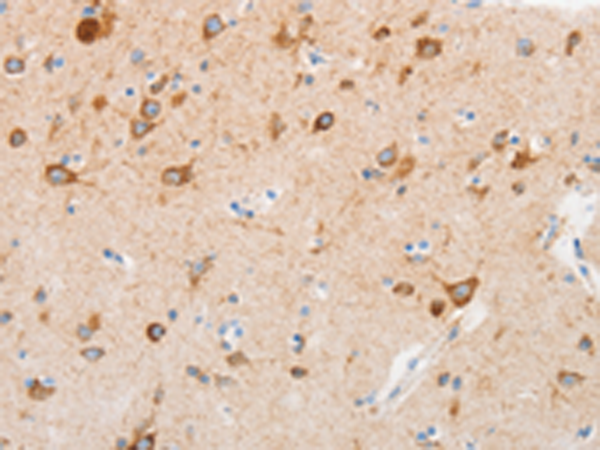

分类: 科研抗体货号: P11271别名: SMRT; TRAC; CTG26; SMRTE; TRAC1; N-CoR2; TNRC14; TRAC-1; SMAP270; SMRTE-tau应用: IHC反应种属: Human

分类: 科研抗体货号: P11251别名: pf16; Repro-SA-1应用: IHC反应种属: Human, Mouse

分类: 科研抗体货号: P11231别名: ACPT; AI1J应用: IHC反应种属: Human, Mouse

分类: 科研抗体货号: P11270别名: 2ADUB, 2A-DUB, RP4-592A1.1应用: WB,IHC反应种属: Human, Mouse

分类: 科研抗体货号: P11250别名: PTA1; DNAM1; DNAM-1; TLiSA1应用: IHC反应种属: Human

分类: 科研抗体货号: P11230别名: C17orf71应用: WB反应种属: Human, Mouse

分类: 科研抗体货号: P11269别名: IRF; SMRZ; MURF1; MURF2; RNF28应用: WB,IHC反应种属: Human, Rat

分类: 科研抗体货号: P11249别名: CR; C3DR; CD21; CVID7; SLEB9应用: IHC反应种属: Human, Mouse

分类: 科研抗体货号: P11229别名: PKX1应用: WB,IHC反应种属: Human

分类: 科研抗体货号: P11268别名: DRCC1, MUC-13应用: IHC反应种属: Human